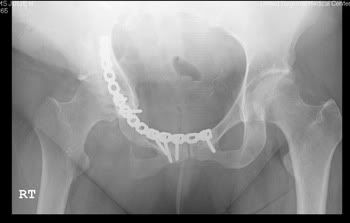

Most people don't understand why I am the way I am. I hope these x-rays give them a better idea of what I have to deal with every single day.

My hip and pelvis